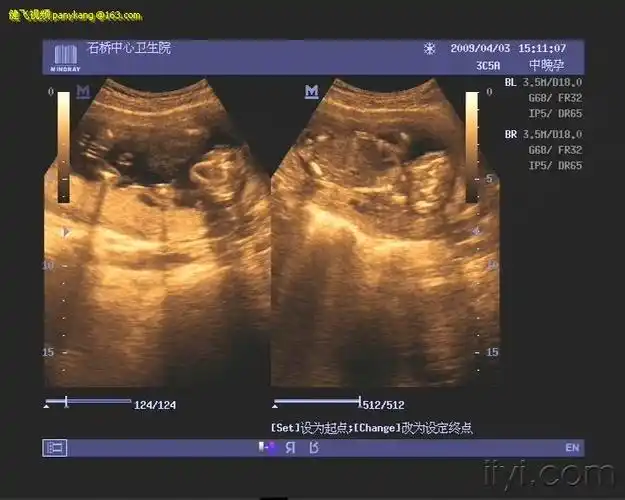

此时期主要进行遗传学超声检查,同时对一些大体结构畸形如无脑儿,联体

胎儿无脑畸形2d4d图

胎儿无叶全前脑的超声病例分享

胎儿无脑畸形

无脑畸形